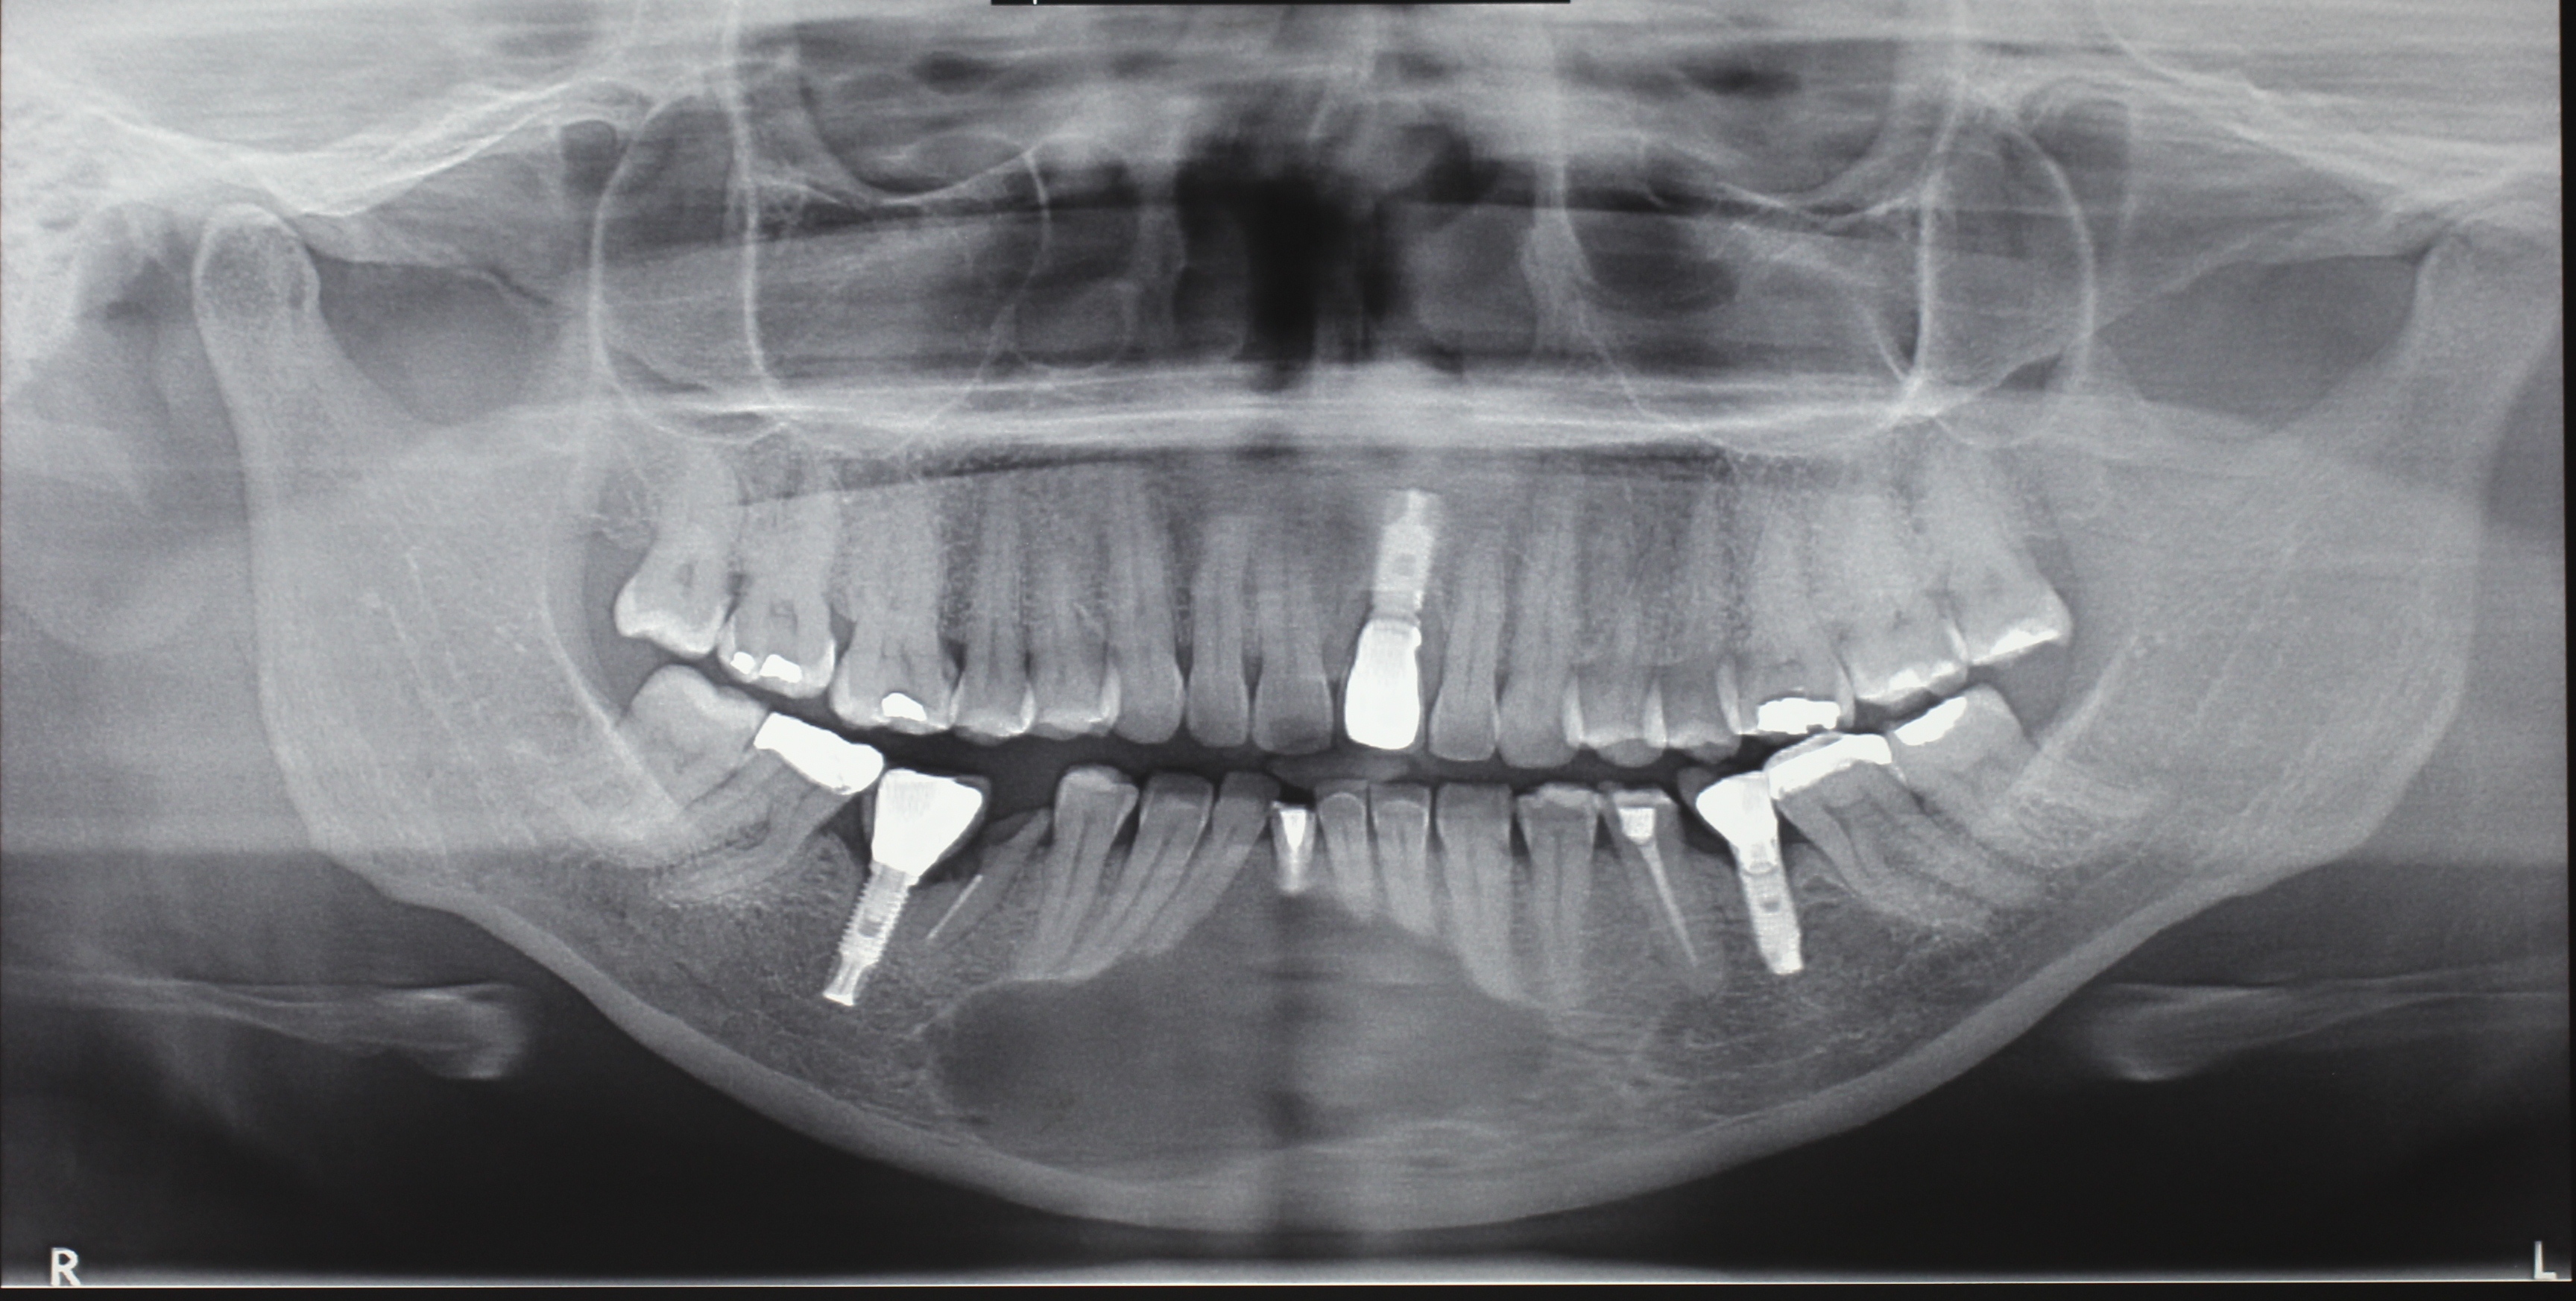

O objetivo deste estudo foi descrever uma técnica de tratamento conservadora, cuja conduta preconizada foi a realização da descompressão seguida pela enucleação cística através do relato de um caso de cisto periapical de grande extensão. Paciente de 50 anos de idade, melanoderma, apresentando cisto periapical com aproximadamente 4,5 cm em seu maior diâmetro associado ao incisivo central inferior esquerdo. Na primeira etapa do tratamento foi realizada descompressão cística e biopsia incisional, cujo exame histopatológico confirmou o diagnóstico clínico. Após 25 semanas de acompanhamento, houve uma considerável regressão do tamanho da lesão e a mesma foi enucleada sem comprometimento dos elementos dentários envolvidos e dos tecidos adjacentes. O relato de caso evidenciou que o tratamento cirúrgico e conservador pode ser um recurso em cistos periapicais de maior dimensão, sendo importante a cooperação do paciente no acompanhamento pós-operatório.

- Figura 1 (Português (Brasil))